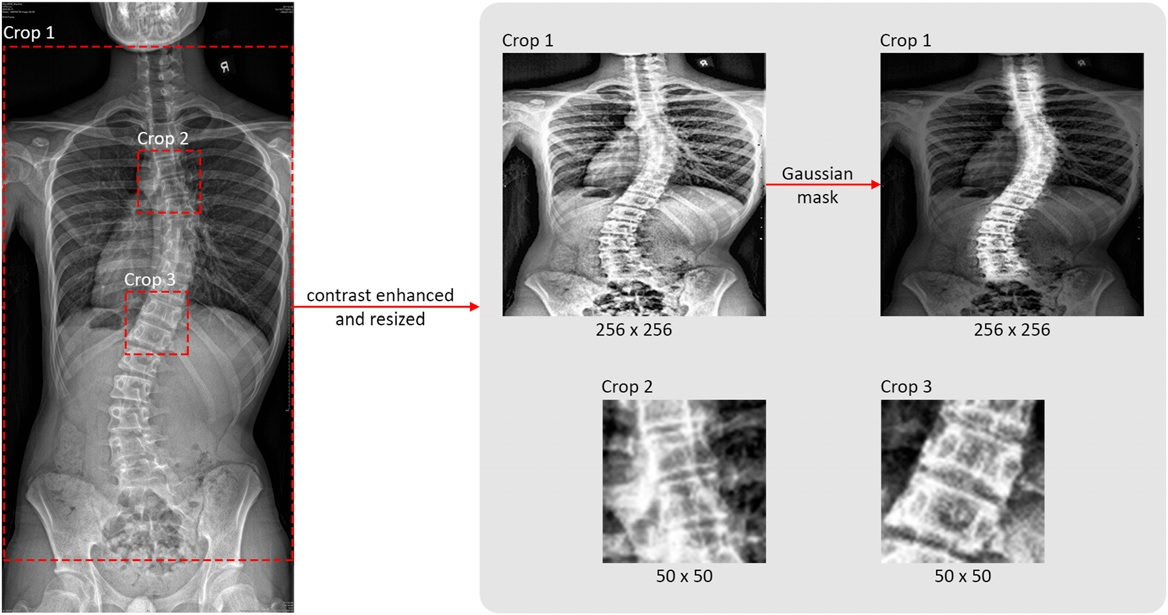

Essentially, the CNN operates in three stages, the authors explained. In the first stage, it identifies the region of interest (ROI), which includes the whole spine with 12 thoracic and five lumbar vertebrae. In the second stage, the four corners of each vertebra are detected as feature points and in the final stage, the model uses the 17 detected feature points to measure the major and minor curves of the Cobb angle.